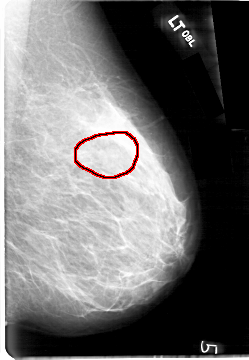

D_4092_1.LEFT_CC

LEFT_CC LINES 5386 PIXELS_PER_LINE 3526 BITS_PER_PIXEL 12 RESOLUTION 43.5 OVERLAY

FILE: D_4092_1.LEFT_CC.OVERLAY

TOTAL_ABNORMALITIES 1

ABNORMALITY 1

LESION_TYPE MASS SHAPE OVAL MARGINS OBSCURED

ASSESSMENT 0

SUBTLETY 4

PATHOLOGY BENIGN

TOTAL_OUTLINES 1

BOUNDARY